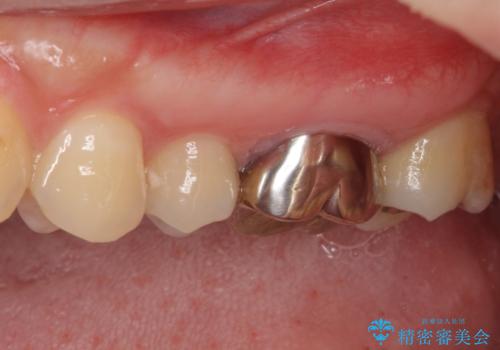

- 奥歯の銀歯の下にあるむし歯治療を希望して来院された患者様です。

口を開けたときに見えてしまう部分はセラミックインレーやジルコニアクラウンに、目立たない部分はゴールドインレーにてむし歯治療を行うこととしました。

機能面を優先すると、PGAインレー(ゴールドインレー)による修復治療やPGAクラウンによる補綴治療が望ましいのですが、笑ったときに見えている銀歯がどうしても気なってしまうとのことで、目立ってしまう奥歯はセラミックインレーやセラミッククラウンを装着することとしました。